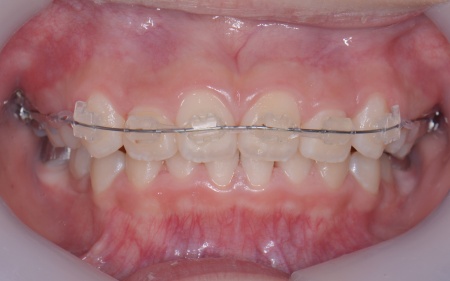

| カウンセリング | 拝見したところ、上の犬歯が歯列の外側に飛び出すように生えている、いわゆる八重歯でした。 さらに、上下の歯全体がデコボコに生えている「叢生(そうせい)」と呼ばれる状態で、これは歯が正しい位置に並ぶためのスペースが不足していることが原因だと考えられます。 このまま放置して顎の成長が完了してから矯正治療を行う場合、歯を並べるスペースを確保することが難しく、永久歯を抜く処置が必要になるケースがあります。 以上のことから、今の段階で歯並びを整える治療が必要だと診断しました。 |

患者様のご家族は「将来的な抜歯はできるだけ避けたいので、今のうちに治療をしたい」と希望されたため、成長期の段階で歯列を広げ、歯が並ぶスペースを確保する小児期の矯正治療「1期矯正」を提案しました。

メリット デメリット また、治療にあたりお口全体のバランスを確認したところ口元の突出はなく、顎のサイズはやや小さめですが、成長期であることから歯列の拡大が可能な状態だと判断しています。 以上の内容について丁寧に説明し、治療に同意いただきました。 まず、上顎に顎の骨を広げるための固定式の矯正器具「急速拡大装置」を、下顎には歯並びの幅を広げるための「リンガルアーチ」を装着します。 次に歯の位置を整えるため、ワイヤー矯正を開始します。 最後に、歯並びが整って見た目や噛み合わせにも問題がないことを確認し、装置を取り外して第1期矯正治療を終了しました。 現在も経過観察を継続していますが、歯が元の位置に戻る後戻りも見られず、残っている乳歯から永久歯への生え変わりも順調に進んでいます。 |